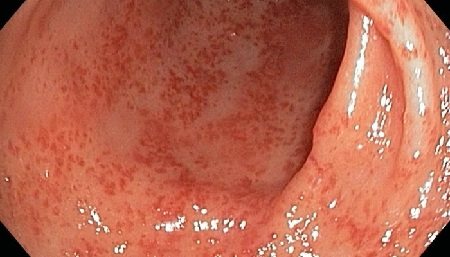

Данный процесс называется кишечная метаплазия. Вначале эти участки слизистой приобретают вид тонкокишечного эпителия, затем толстокишечного. Чем дальше зашел процесс метаплазии, тем больше вероятность развития аденокарциномы желудка. На сегодняшний день хеликобактерная инфекция включена в список биологических канцерогенов, ведь без надлежащего лечения она рано или поздно приводит к раку желудка.

Изменения слизистой

Атрофические процессы в толще и на поверхности слизистой оболочки приводят к тому, что на месте железистого эпителия образуется соединительнотканный рубец или начинают расти клетки, характерные для эпителия кишечника. Результатом трансформации станет неспособность желудка вырабатывать необходимое количество пищеварительных ферментов, ионов водорода и хлора. Показатель уровня кислотно-щелочного равновесия ощутимо повышается и процессы обработки пищи в желудке становятся хуже. В результате пищевой комок продвигается дальше в необработанном виде. Перечислены главные причины атрофического гастрита.

В ходе диагностических исследований хронический атрофический гастрит проявляется следующими признаками:

- обычной или истонченной стенкой органа;

- сглаженной слизистой оболочкой;

- широкими желудочными ямочками;

- уплощением эпителия;

- низкой секреторной активностью желез;

- умеренной инфильтрацией лейкоцитов за пределы сосудов;

- дегенерацией (вакуолизацией) клеток желез.